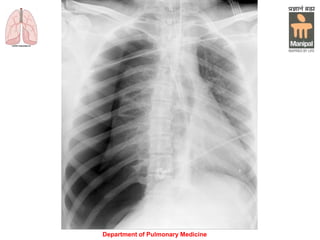

Chest X-ray:

Blunting of the sharp costophrenic angle.

Up to 300 mL of fluid may fail to be seen on a PA

chest radiograph, whereas as little as 150 mL may

be seen on a lateral decubitus view.

A supine film (e.g. in ICU patients) may obscure the

diagnosis because the fluid layers posteriorly.

A pseudotumor occurs when fluid loculates in an

interlobar fissure, a clue to the diagnosis is the

presence of pleural fluid elsewhere and a biconvex

lenticular configuration of the mass.